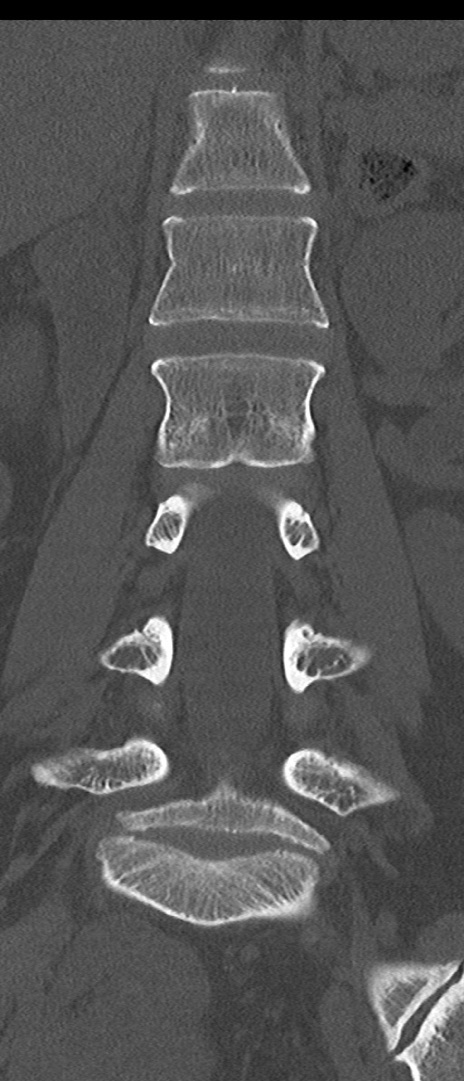

【整形】TIPS症例4 腰椎CT(冠状断像)

腰椎CT

矢状断像